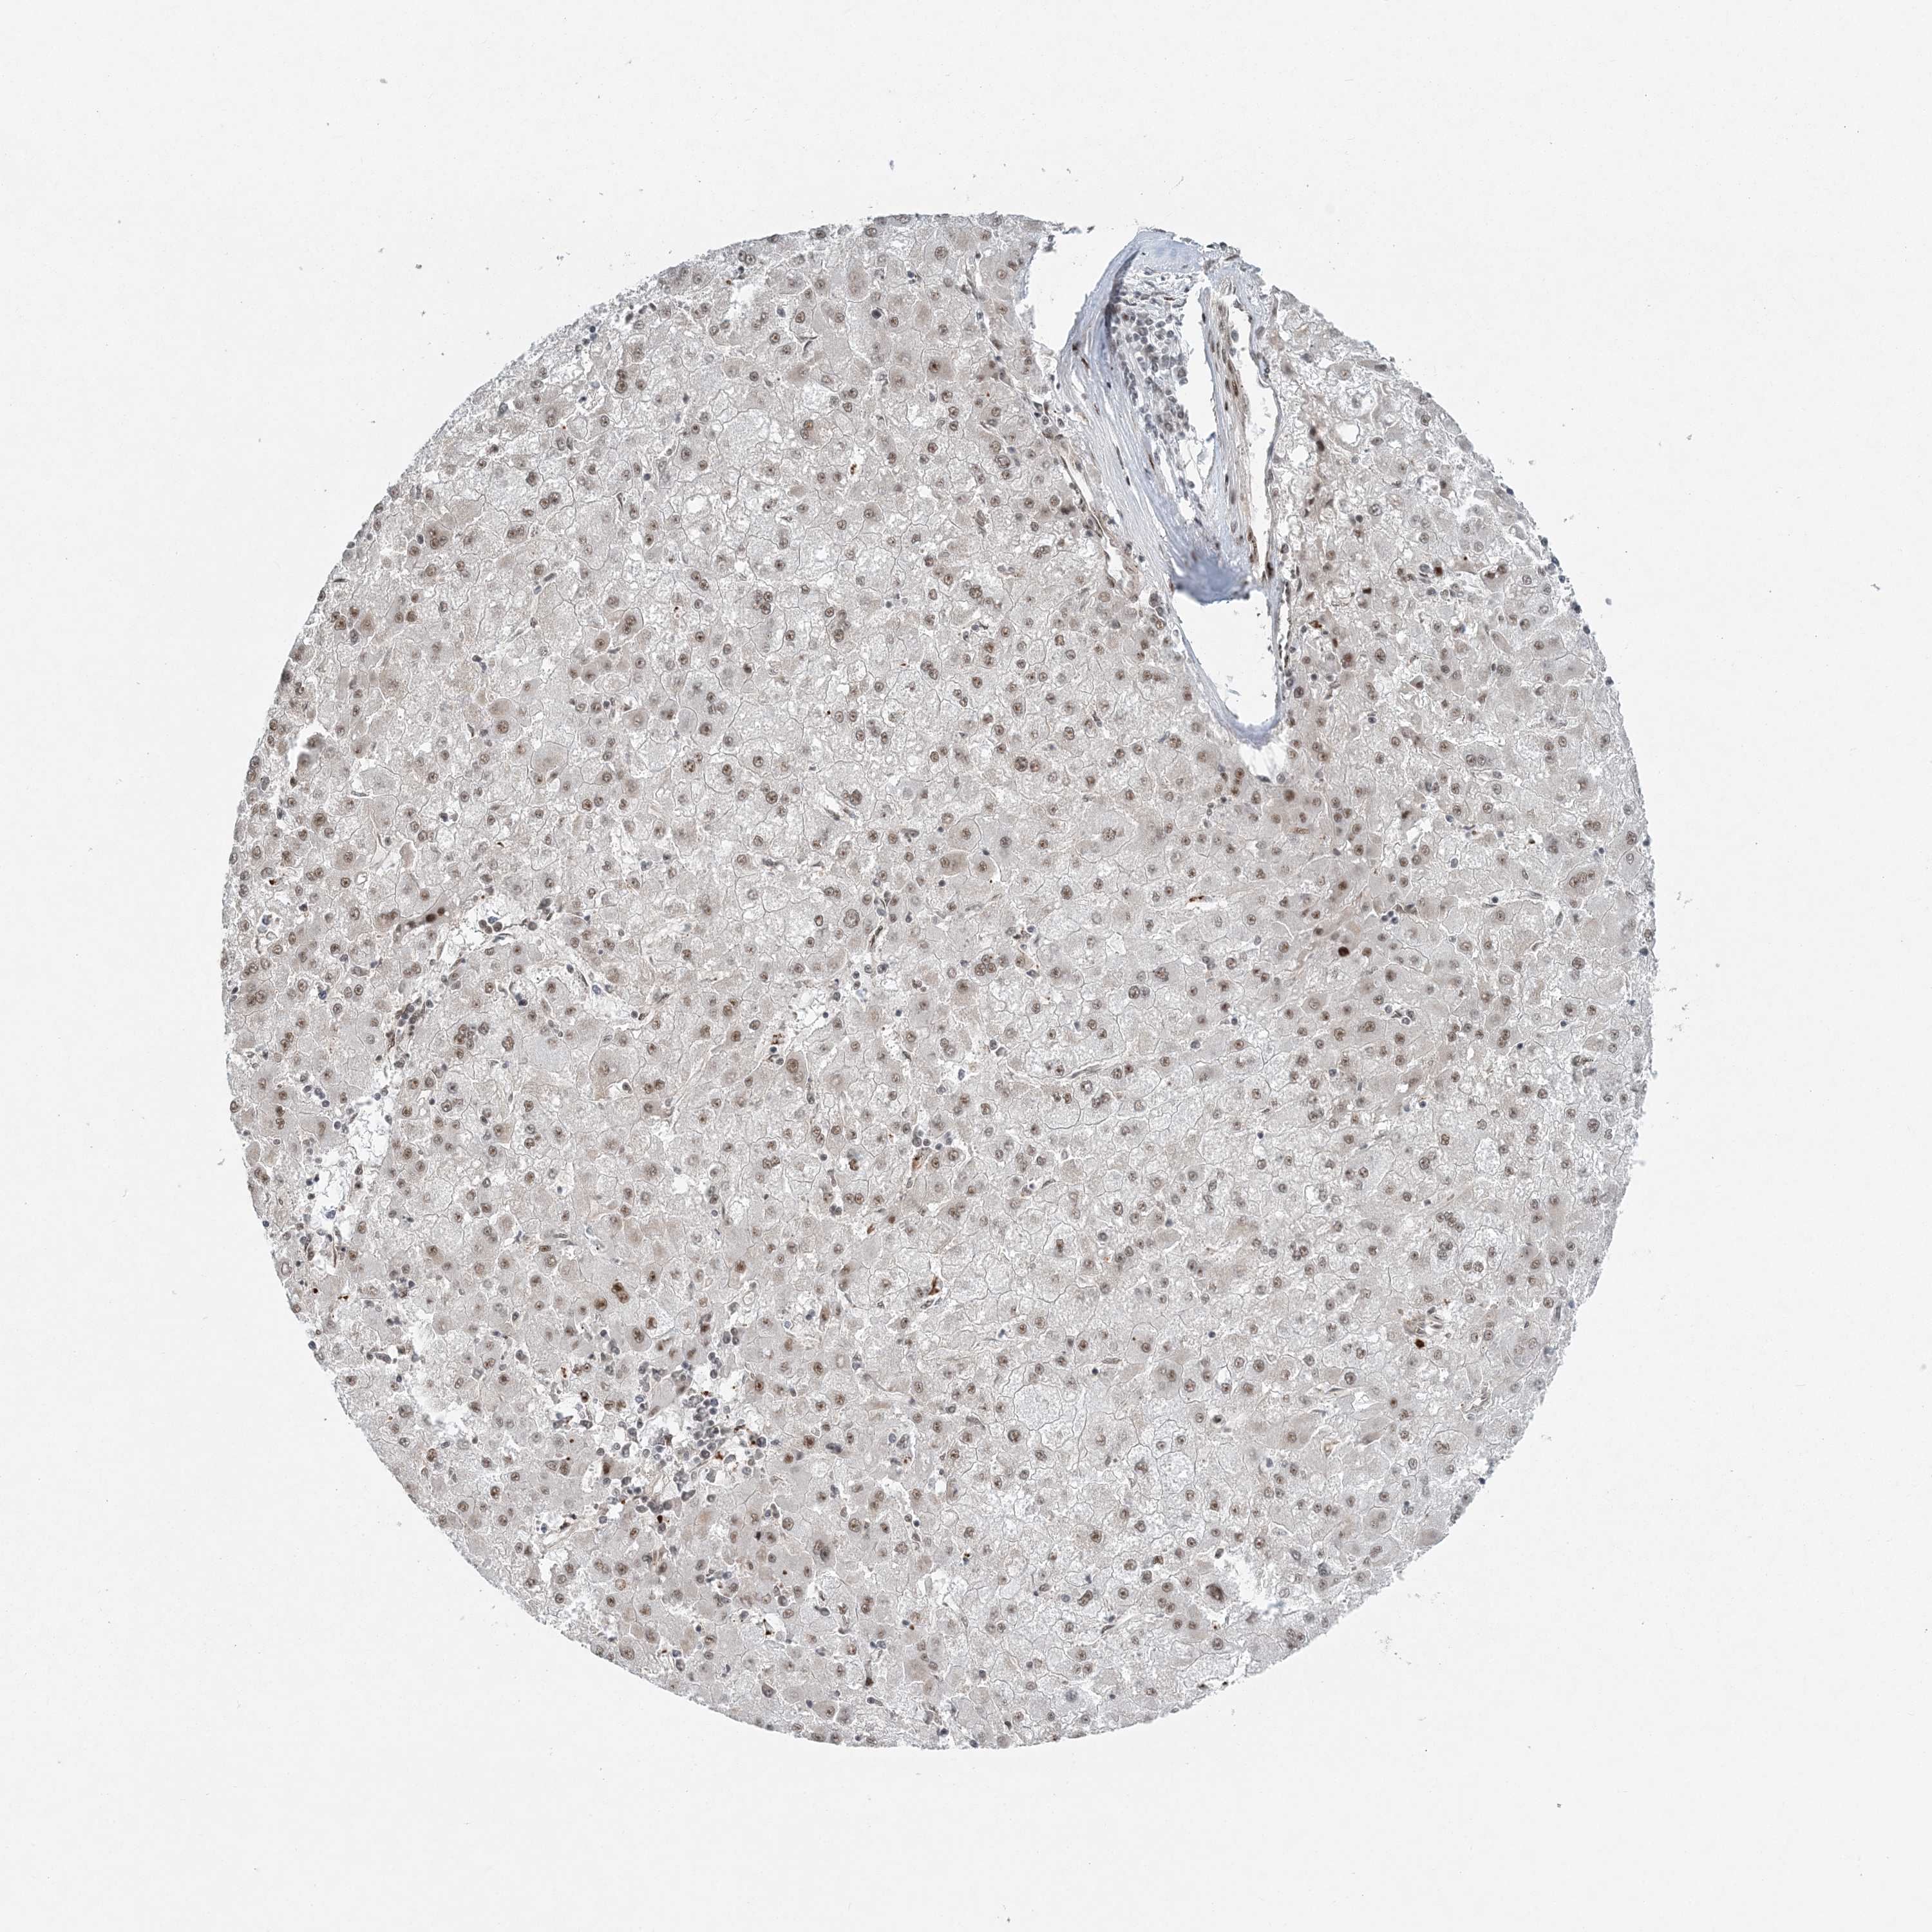

LIVER CANCER - Protein expressioni

A mouse-over function shows sample information and annotation data. Click on an image to view it in a full screen mode. Samples can be filtered based on level of antibody staining by selecting one or several of the following categories: high, medium, low and not detected. The assay and annotation is described here.

Note that samples used for immunohistochemistry by the Human Protein Atlas do not correspond to samples in the TCGA dataset.

Antibody stainingi

Antibody staining in the annotated cell types in the current human tissue is reported as not detected, low, medium, or high, based on conventional immunohistochemistry profiling in selected tissues. This score is based on the combination of the staining intensity and fraction of stained cells.

Each image is clickable and will lead to virtual microscopy that enables deeper exploration of all samples and also displays staining intensity scores, fraction scores and subcellular localization as well as patient and tissue information for each sample.

Antibody HPA036748

Staining

High

Medium

Low

Not detected

Intensity

Strong

Moderate

Weak

Negative

Quantity

>75%

75%-25%

<25%

None

Location

Nuclear

Cytoplasmic/membranous

Cytoplasmic/membranous,nuclear

Cholangiocarcinoma

Carcinoma, Hepatocellular, NOS